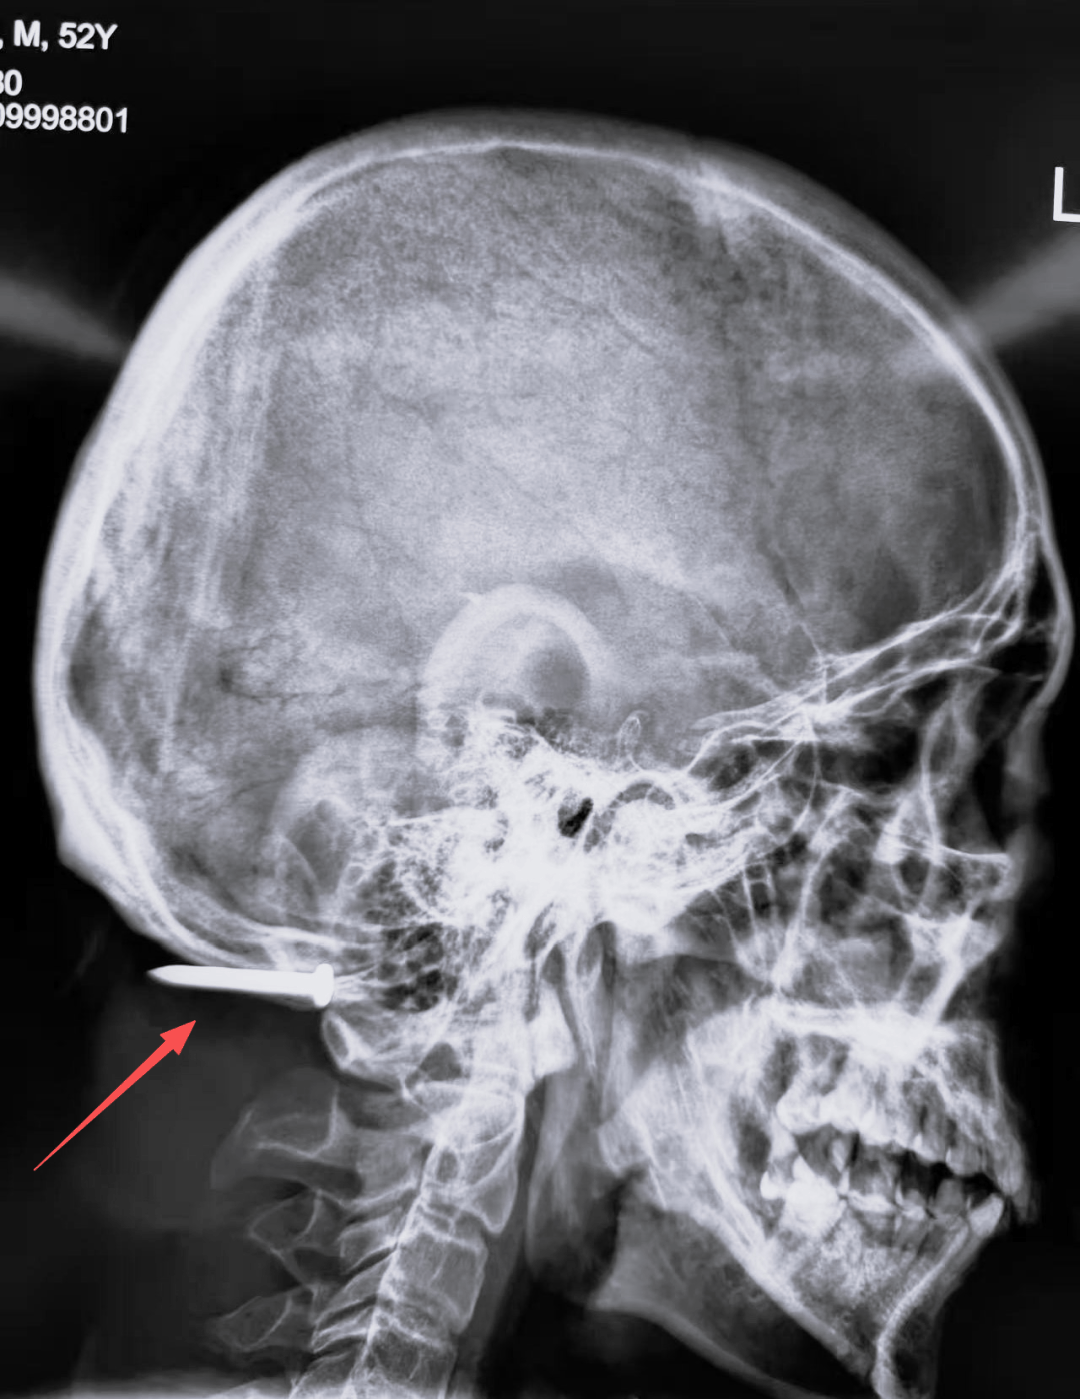

2025年11月12日中午1点,急促的救护车鸣笛声打破了北京积水潭医院回龙观院区的宁静。一名52岁男性患者被紧急送进急诊抢救室,一枚水泥钢钉从的他面部射入,贯穿颅颈部位,生命危在旦夕。

经急诊医师问诊得知,患者是一名工人,作业时不慎被射钉枪击中。射钉枪常用于钢筋混凝土施工,枪口动能巨大,导致钢钉从其左侧下颌射入,先后穿透下颌骨、口腔、颈椎间隙,最终深嵌枕部颅骨下方。伤后患者随即出现呕血症状,虽辗转多家医院,却因病情复杂、手术风险极高,最终被转至北京积水潭医院。

图说 / 患者术前影像(红色箭头为钢钉位置)